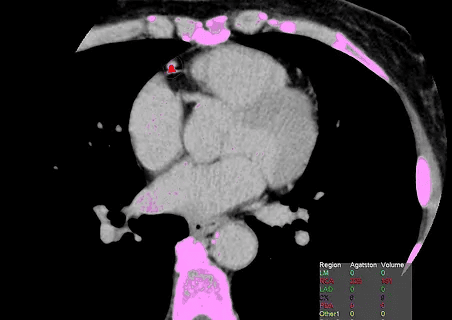

É um teste não invasivo, que não utiliza contraste iodado, realizado através de tomógrafo multi-detectores de última geração com baixíssima dose de radiação. Permite ao médico a detecção precoce de calcificação nas artérias coronárias, identificando indivíduos de maior risco para eventos cardíacos futuros (infarto ou angina), mesmo que assintomáticos.